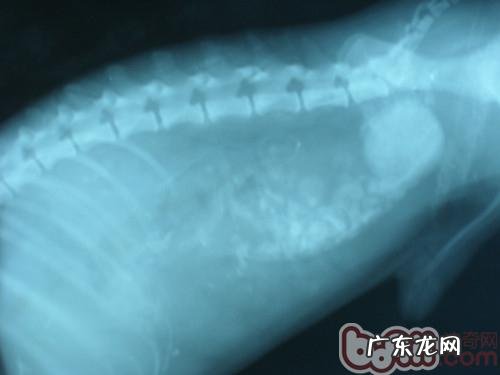

这个是肠道梗阻的又一病案,阻塞的位置相邻肛门口 。

文章插图

肠道梗阻